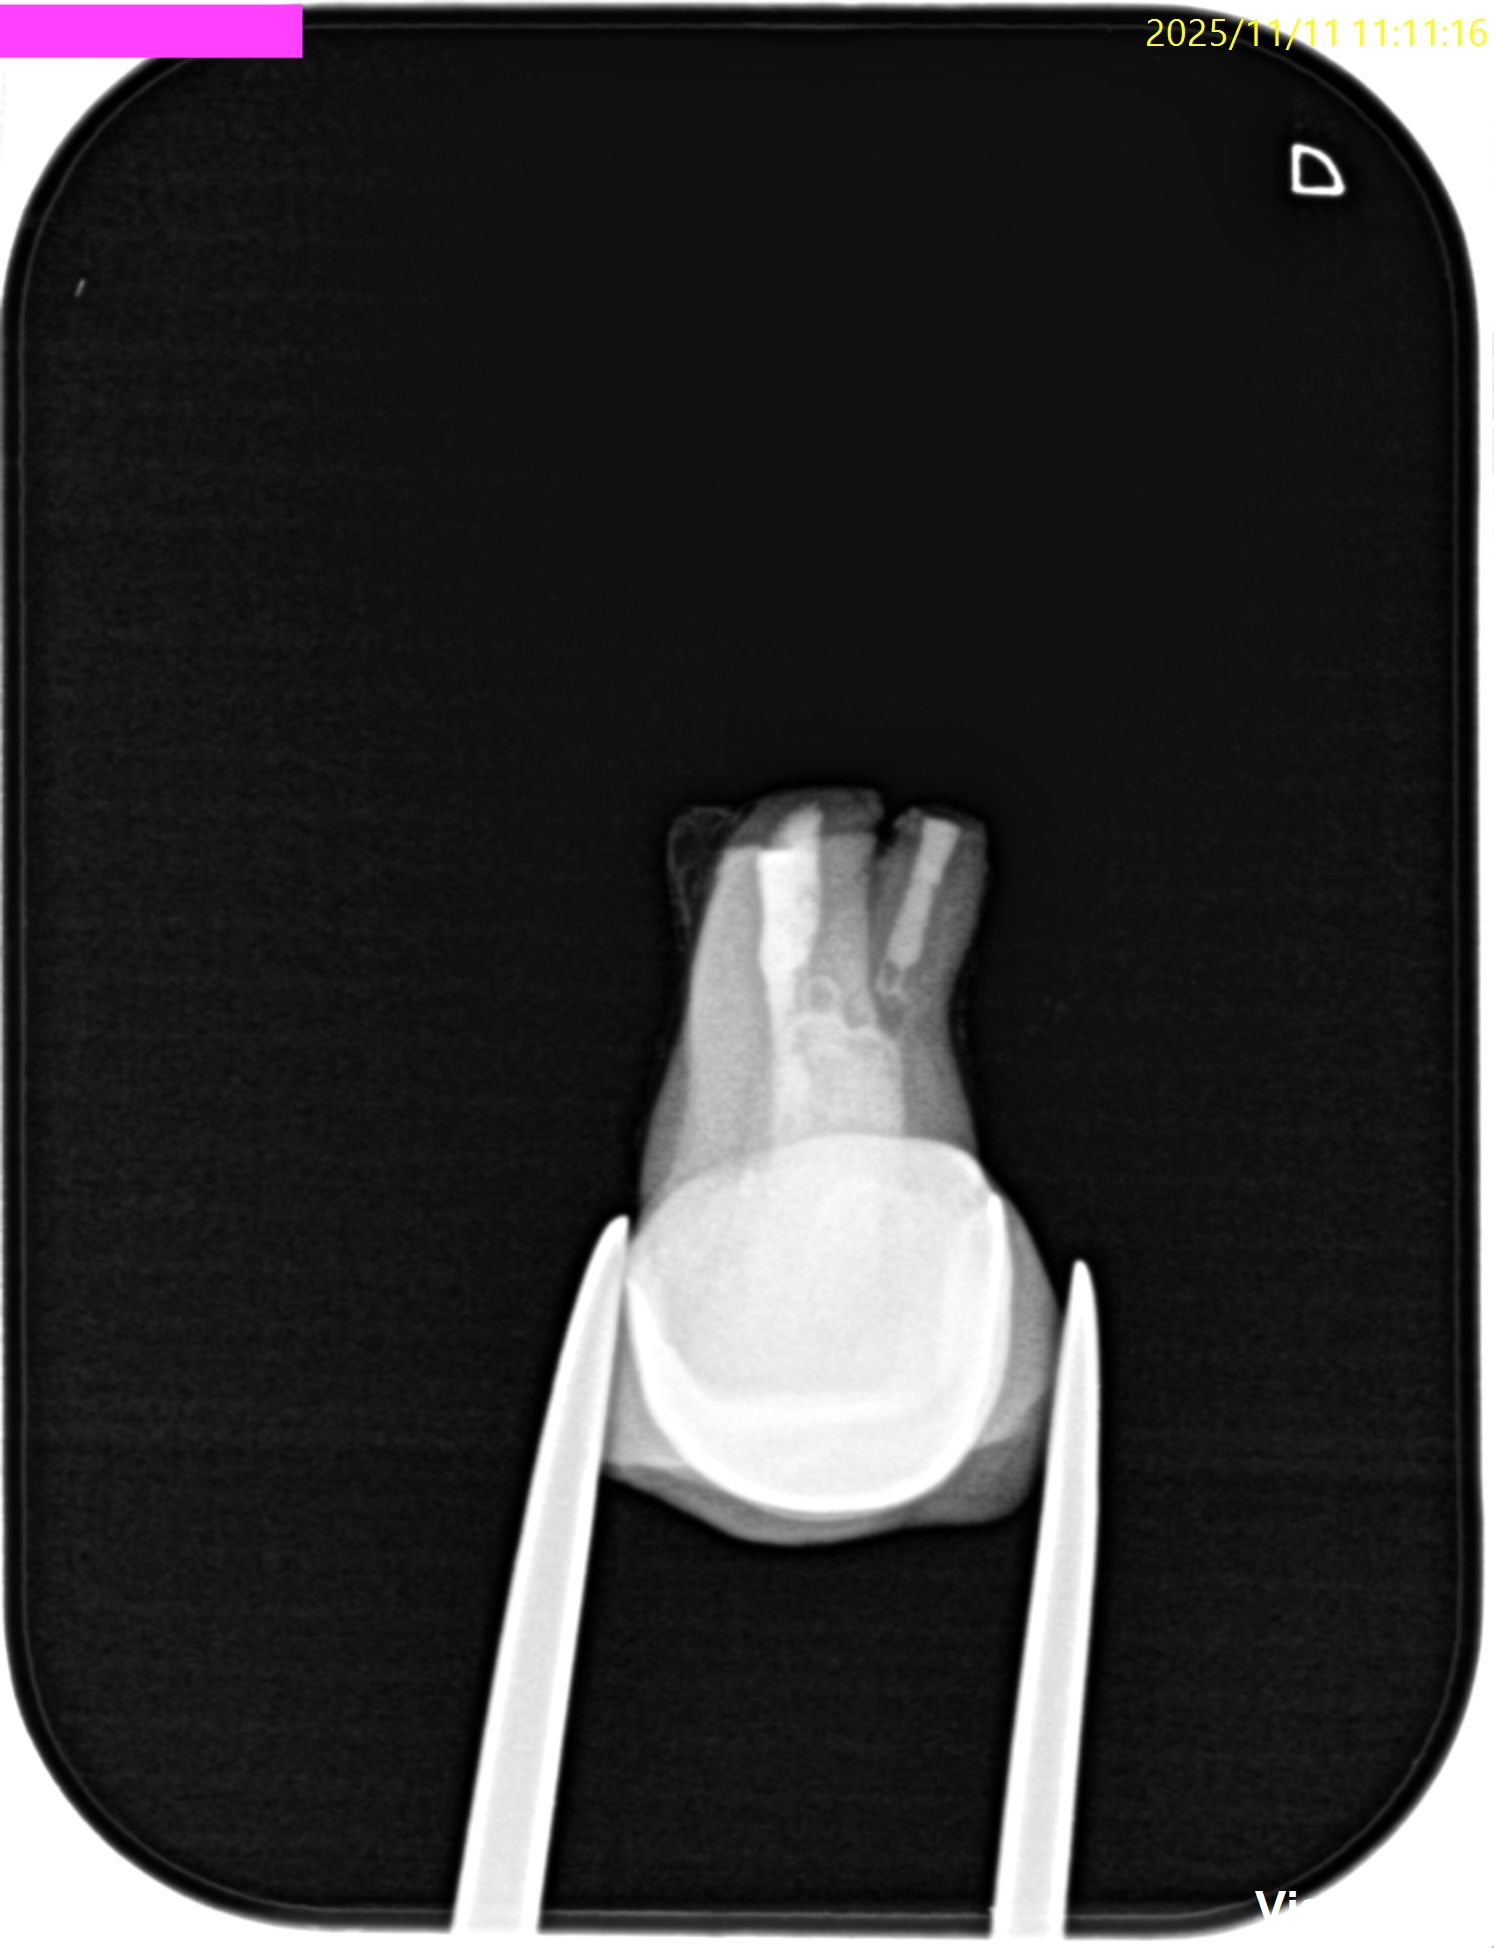

PA(2025.11.11)